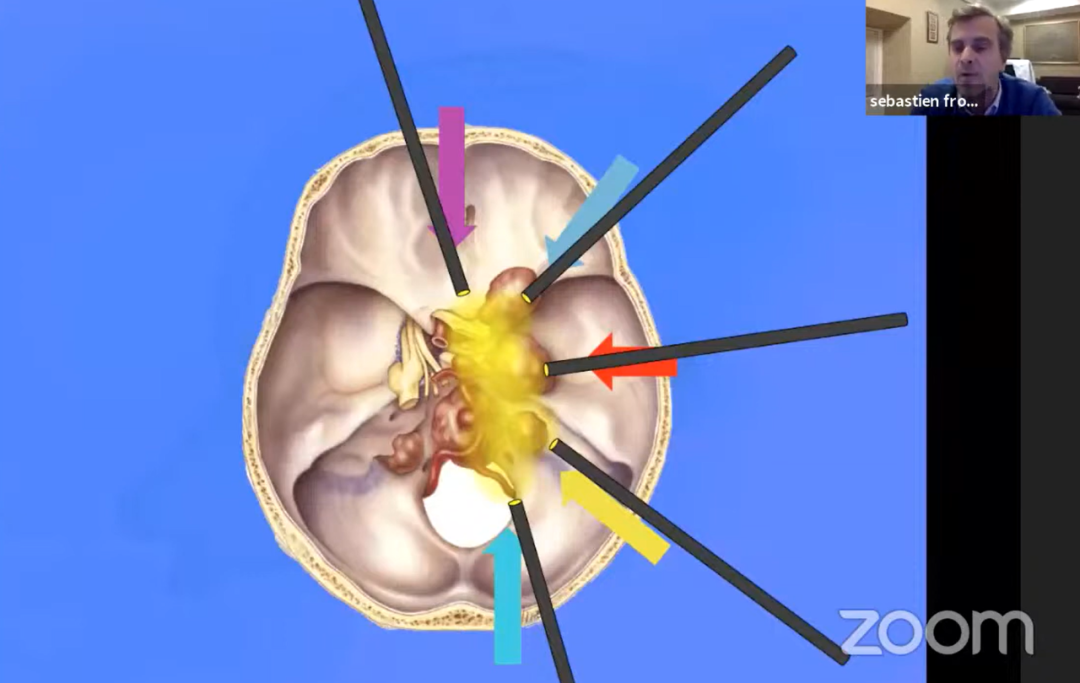

第一阶段,采用经神经内镜经鼻入路,对视交叉和神经进行减压,为后续处理奠定基础。然而随着肿瘤加速生长,新的视觉缺损相继出现,对下丘脑和第三脑室的压迫持续加重,需要再次手术切除。第二阶段,经后岩骨入路(即后迷路经天幕入路)可充分暴露肿瘤及周围解剖结构,包括第三脑室底部及侧壁、分支血管、视神经等。

手术过程中详细处理了后岩骨入路的相关技术要点及术中解剖细节,涵盖横窦-乙状窦连接部的后方移位、天幕切开时静脉结构的保护方式、肿瘤切除过程中第三脑室底部的辨认与保护,以及精细的多层次缝合关闭等步骤。

颅咽管瘤的起源部位决定了其周边的重要解剖结构,包括视神经、垂体柄、下丘脑,以及颈内动脉分支、基底动脉分支——尤其是基底动脉、后交通动脉和大脑后动脉与肿瘤的关系往往极为紧密,此外还涉及脑干等结构。视神经关系视力,垂体柄影响内分泌,下丘脑决定患者的认知能力和术后内分泌功能,脑干是人体"生命中枢",颈内动脉、基底动脉等大血管则统管全身血液运输。手术切除过程中一旦损伤上述重要结构,可能引发灾难性且不可逆的神经功能损害。